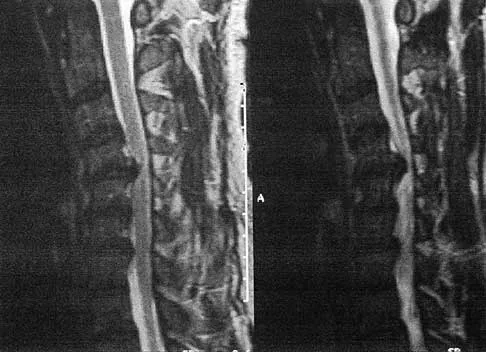

Question 51High Yield

A 50-year-old man with no history of trauma reports new-onset back pain after doing some yard work the previous day. He reports pain radiating down his leg posteriorly and into the first dorsal web space of his foot. MRI scans are shown in Figures 3a through 3c. What nerve root is affected?

Explanation